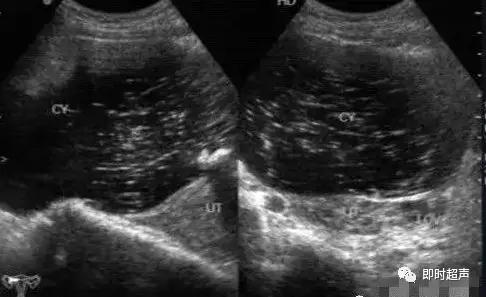

卵巢成熟囊性畸胎瘤(mature teratoma):常见,声像图表现多种多样。

卵巢畸胎瘤声像图,因其构成成分及比例不同而表现不一,可表现为“脂液分层征”、“面团征”、“瀑布征”、“雪花征”、“线条征”、“壁上结节征”、“杂乱结构征”7种特异性声像图。